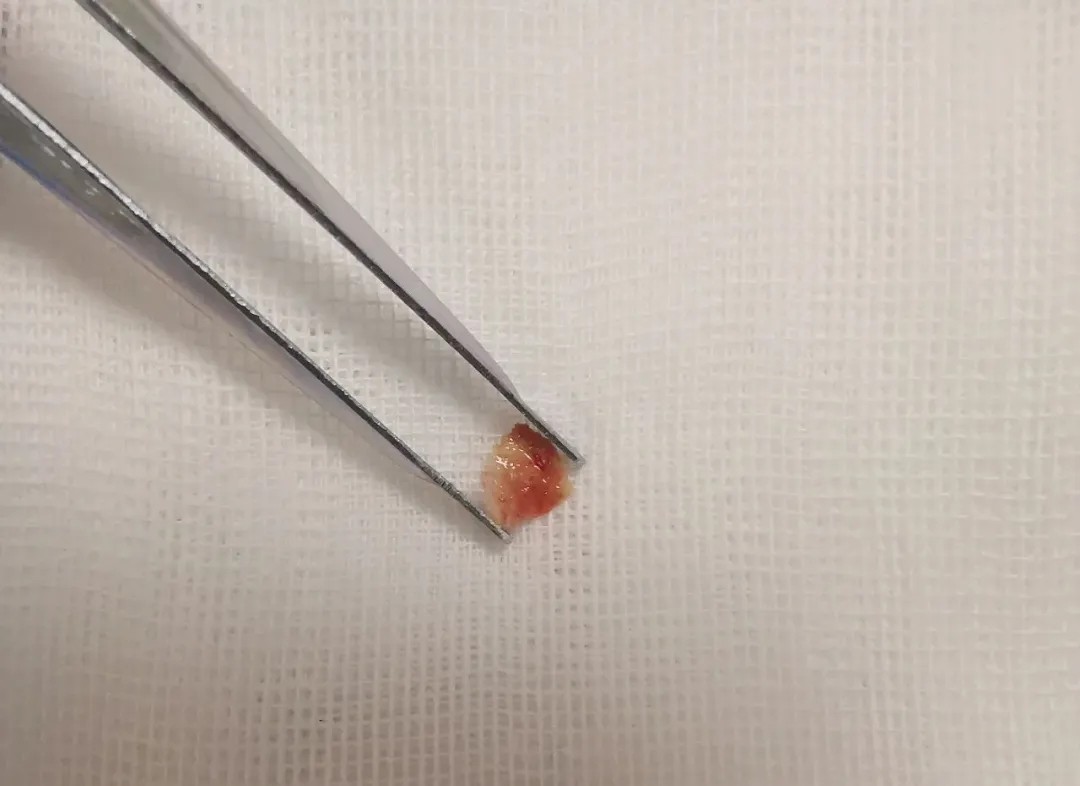

在使用活检钳多次钳取开口处新生物,并扩大视野后,终于发现了使患者支气管闭塞的罪魁祸首——骨头碎片!

发现骨头碎片

由于骨头碎片的形状不规则,且在气管内的时间较长,已经与气管内组织粘连,变得非常酥软,导致夹取较为困难。经过1个多小时的紧张操作,一块约3mm的骨头碎片终于被顺利取出。

取出骨头碎片